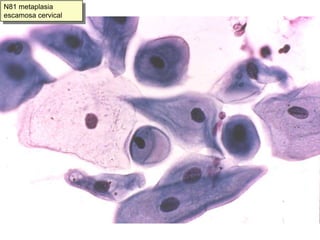

Metaplasia escamosa y zona de transformaciónLa zona de transformación , o unión de epitelios endocervical y exocervical, debe ser muestreada siempre.Por eso debe haber:Células endocervicalesO células de la zona de transformación:Hiperplasia de células de reservaO metaplasia escamosaLa metaplasia escamosa es un proceso patológico que incluimos entre la normalidad celular por su frecuencia en mujeres en edad fértil con ectropion

N81 metaplasia escamosa cervical